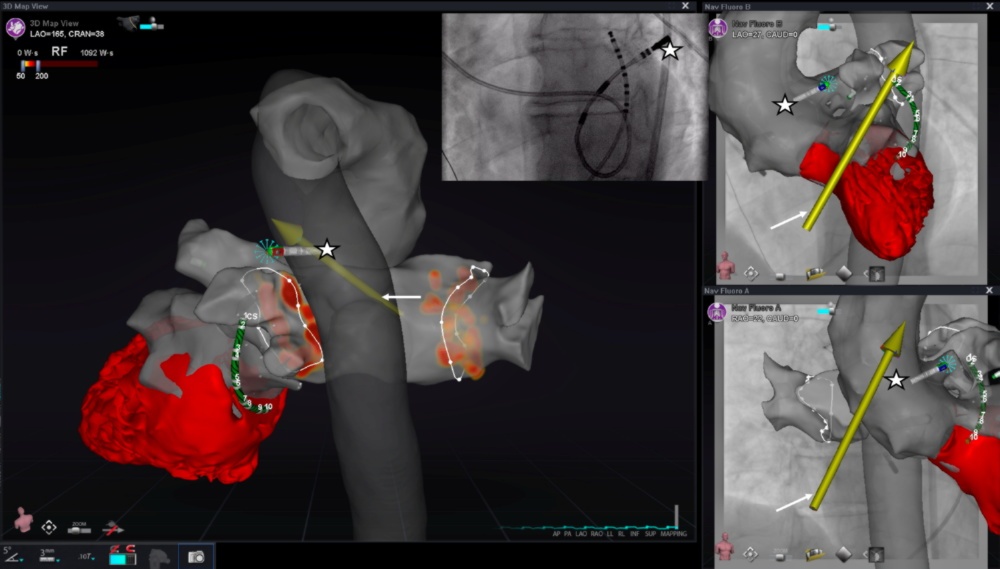

На рисунке представлена 3D-реконструкция аорты, левого предсердия и левого желудочка сердца (отмечен красным), созданная с помощью системы роботизированной магнитной навигации с использованием данных компьютерной томографии и рентгенографии. Звездочкой отмечен аблационный электрод, с помощью которого была выполнена радиочастотная аблация фибрилляции предсердий. Стрелкой обозначен вектор управления катетером с помощью системы роботизированной магнитной навигации. Оранжевые точки – места аблационных воздействий в левом предсердии.